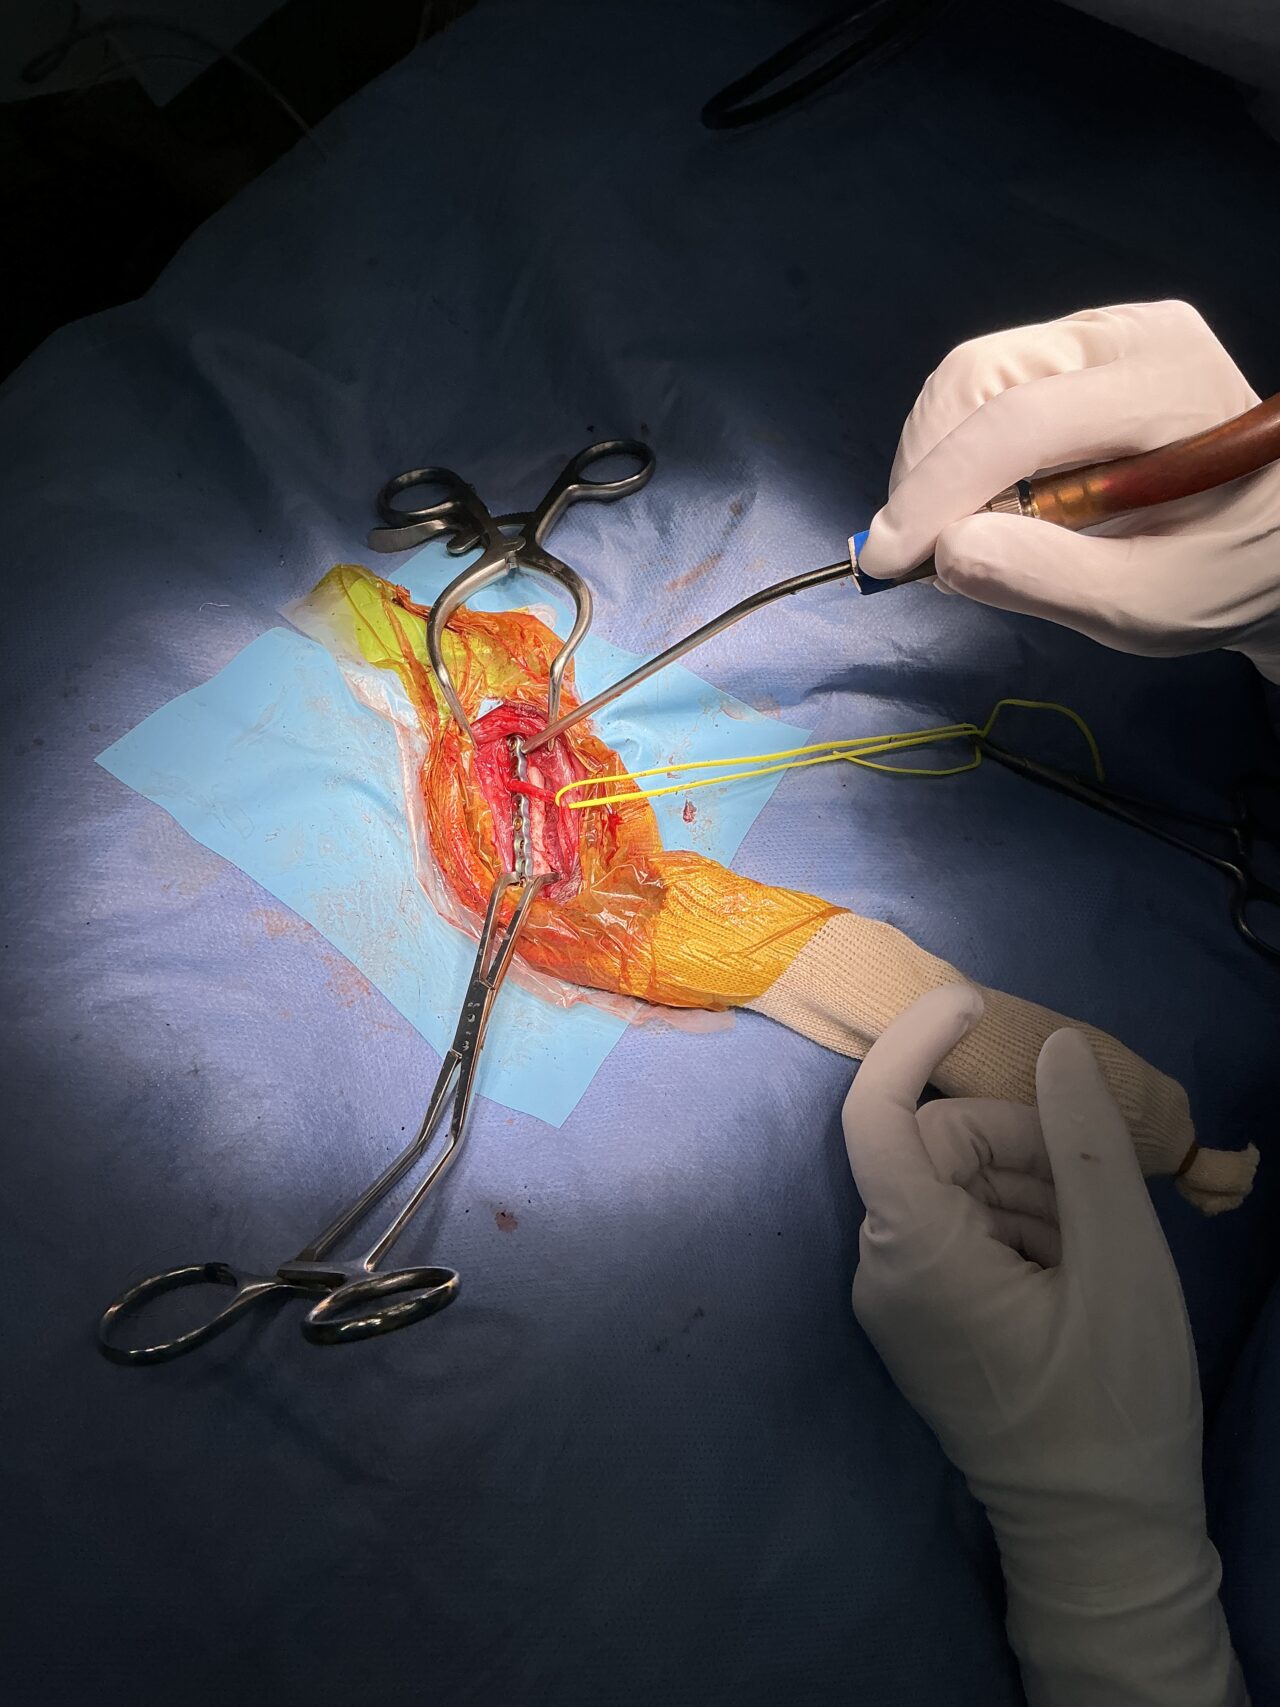

若い猫ちゃんが部屋で遊んでいたところ、不運にも上腕骨を粉砕骨折してしまったとのこと。かかりつけ医から固定術の依頼がありました。粉砕部分をOrthogonal Plateで固定術を行いました。